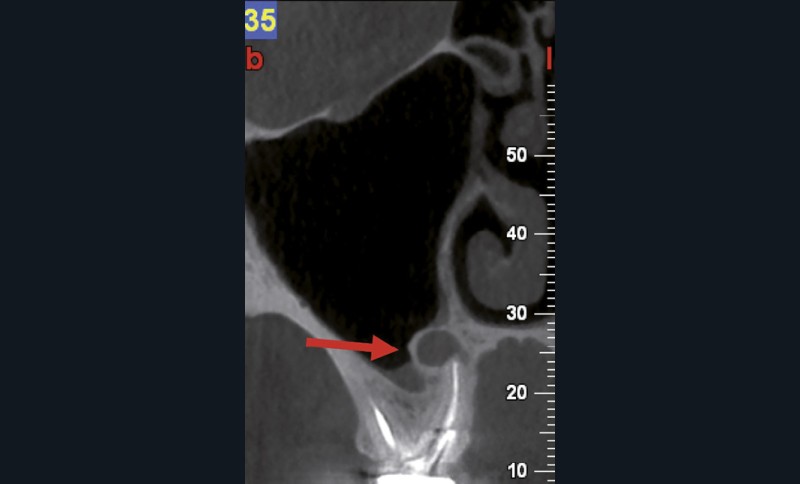

Si les isthmes sont particulièrement mis en évidence au niveau des molaires mandibulaires, cela devient médicalement important au niveau des molaires maxillaires.

La diffusion bactérienne et de leurs toxines, au niveau des molaires maxillaires est à l’origine d’un grand nombre de sinusites maxillaires chroniques, d’origine dentaire. Celles-ci sont principalement causées par l’absence de traitement du deuxième canal MV, qui existe dans 90 % des cas, et il est à noter que ces deux canaux – MV1 et MV2 – sont également reliés par un isthme.

Le nettoyage des isthmes intercanalaires reste un réel problème, et semble responsable de nombreux échecs [43]. Par ailleurs, il est nécessaire d’utiliser des instruments qui évitent de propulser les débris, tant apicalement que latéralement, en obturant les entrées isthmiques avec des débris compactés.

L’utilisation d’instruments en nickel titane, tels que le XP Shaper (FKG), le Vortex blue (Dentsply) ou le Profile (Dentsply), optimise la remontée des débris et s’inscrit dans cette nouvelle philosophie. En conséquence, la combinaison XP Shaper, XP Finisher et l’irrigation avec l’Er:YAG semblent optimiser nos traitements [44,45].

Le passage du laser est répété plusieurs fois, en début, au milieu et en fin de préparation. Un protocole peut alors être proposé : 40 mJ ; 20 Hz (fig. 7). L’utilisation de biocéramiques Bioroot (Septodont) ou Total Fill R (FKG) permet de sceller le système ainsi nettoyé, en assurant une action biologique de longue durée [46] (fig. 8a à c).